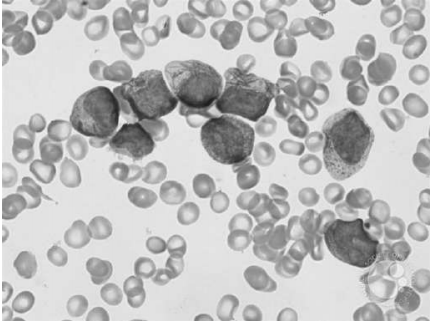

Uma paciente de 16 anos de idade apresenta quadro de aparecimento de equimoses em membros inferiores há cerca de três semanas, menorragia, astenia e fadiga. O hemograma realizado indica leucócitos = 500/mm3 , Hb = 6,2 g/dL, Ht = 18,4% e plaquetas = 23.000/mm3 , e o resultado dos exames de coagulação com dosagem de fibrinogênio é de 80 mg/dL. A imunofenotipagem da medula óssea mostra 85% de células com complexidade intermediária a alta e fraca expressão de CD45, correspondendo a blastos que expressavam CD13, CD33 (forte), CD38, CD64 (fraco), CD117 e MPO, sem expressão de CD2, CD11b, CD15, CD34, HLA-DR ou demais marcadores pesquisados. O mielograma pode ser observado a seguir.

Disponível em:<https://imagebank.hematology.org/collection/5910> . Acesso em: 8 jan. 2021.

Com base nesse caso clínico, na imagem apresentada e nos conhecimentos médicos correlatos, julgue os itens a seguir.

Esse tipo de leucemia aguda é caracterizada pela presença da alteração citogenética inv (16).